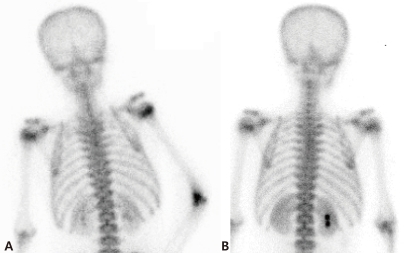

A 13 year-old boy presented with fever and not swollen discomfort of the right elbow without swelling and tenderness. Four months previously, he had been diagnosed to have Ewing sarcoma of the right ilium and had undergone five cycles of preoperative chemotherapy. He had contracted a C. tropicalis urinary tract infection during a febrile neutropenia episode after chemotherapy, which was treated with itraconazole and broad spectrum antibiotics for 7 days. No growth was reported in the last urine culture after itraconazole treatment. Recently, he had been on preoperative chemotherapy (vincristine, ifosfamide, doxorubicin, and etoposide), which he had completed 9 days prior to presentation.At presentation, his body temperature was 37.5℃, pulse rate 120 per minute, respiration rate 20 per minute, and blood pressure 130/70 mmHg. physical examination revealed a slight throat infection, but no sinus tenderness, nor tonsilar nor lymph node enlargement. Heart and lung sounds were normal, liver and spleen were non-palpable, and no edema or pain was found in the lower extremities. He complained of discomfort of the right elbow. Laboratory tests revealed pancytopenia, and complete blood count findings were leukocytes 160/mm3, absolute neutrophil count 40/mm3, hemoglobin 9.4 g/dL, and platelet count 8,000/mm3. Broad-spectrum antibiotics (piperacilin/tazobactam and isepacin) were immediately administered after obtaining blood and urine for culture studies.After two days of antibiotic treatment, mild tenderness and swelling (without heating sensation) were detected on the right elbow. A simple radiograph obtained on the 3rd hospital day revealed soft tissue swelling with a positive fat pad sign (Fig. 1). Ultrasonography on the 4th hospital day showed soft tissue edema and articular effusion, and subsequently, 15 mL of yellowish fluid was aspirated from the joint and cultured (Fig. 2). A three phase bone scan (Fig. 3) performed on the 6th hospital day for the differential diagnosis of tumor metastasis and infection showed a limited region of uptake on the right elbow, suggesting the possibility of arthritis.The symptoms and signs of arthritis aggravated despite a 10-day course of broad-spectrum antibiotics. On the 11th hospital day, cultures of synovial fluid and tissue demonstrated the presence of C. tropicalis. However, blood and urine culture specimens were negative. Follow-up right upper elbow ultrasonography on the 11th hospital day showed elbow articular space effusion and hypertrophic synovium. Emergent decompression was performed on the same day, and a drain tube was placed in the right elbow articular space. During the operation, 2 mL of a yellowish-red turbid synovial fluid sample was obtained and submitted for culture, which later confirmed the presence of C. tropicalis. In addition, abdominal computed tomography on the same day showed no evidence of hepato-splenic candidiasis.Intraveneous itraconazole 400 mg/day (5 mg/kg/day) was started on the 11th and 12th days. Intravenous itraconazole was decreased to 200 mg/day on the 13th day and then kept at the same dose. Fever, joint swelling, and arthralgia gradually resolved after itraconazole treatment, and after 2 weeks of intravenous itraconazole treatment on the 25th hospital day. Intravenous itraconazole 200 mg/day was substituted for oral itraconazole solution at 200 mg/day.The antifungal treatment was maintained for three months, and from 14 days after treatment commencement the patient had no elbow pain and was without disability. Furthermore, no relapse of the fungal arthritis occurred during oral itraconazole therapy. Simple radiography and a bone scan carried out after 3 months of antifungal treatment showed no abnormal lesion related to septic arthritis, and oral itraconazole was discontinued.

Fig. 1

Lateral view of the right elbow shows soft tissue swelling with a positive fat pad sign (arrow head).